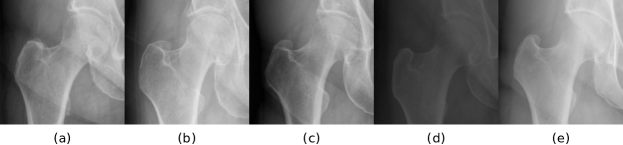

Refer to caption

Fig. 10: Five exemplar images from the hip training set. (a) The exemplar image automatically selected using the proposed method. (b)-(e) Four randomly selected exemplars.

3.7.2 Impact of the selection of the exemplar image

Since the exemplar image is the main source of supervision signal, the selection of the exemplar image may be critical to the generalizability of CTN. In Section 3.1.1, we propose to select the image with the minimum average VGG distance to other training images as the exemplar. In this section, we conduct experiments on the hip dataset to evaluate CTN’s performance using four randomly selected exemplars and compare them with the automatically selected exemplar. The five exemplar images are shown in Fig. 10, and their resulting performances are reported in Table 5. We can observe that the automatically selected exemplar Fig. 10(a) based on VGG distance results in better performance than the randomly selected ones. We also observe that the performance of CTN is not always correlated with the VGG distance. For example, the exemplar Fig. 10(d) with larger distance produces a better CTN model than Fig. 10(e) with smaller distance. We note that even with randomly selected exemplars, CTN consistently outperforms previous one-shot segmentation methods, e.g. Brainstorm.